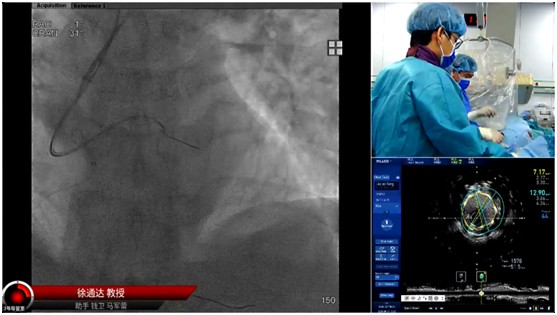

本屆大會(huì)的一大亮點(diǎn)當(dāng)數(shù)CTO手術(shù)演示環(huán)節(jié),CTO病變被視為冠心病介入治療領(lǐng)域的 "最后堡壘"。大會(huì)特邀多位國(guó)內(nèi)CTO介入領(lǐng)域頂尖專(zhuān)家同臺(tái)競(jìng)技,進(jìn)行了16臺(tái)高難度手術(shù)的實(shí)時(shí)直播演示,受到業(yè)內(nèi)普遍關(guān)注及高度評(píng)價(jià)。本次手術(shù)演示不僅展示了徐醫(yī)附院心內(nèi)科在區(qū)域內(nèi)雄厚的技術(shù)實(shí)力,更通過(guò)病例討論、技術(shù)培訓(xùn)等環(huán)節(jié),推動(dòng)先進(jìn)經(jīng)驗(yàn)向基層輻射。參會(huì)的基層醫(yī)師普遍表示,專(zhuān)家們對(duì)復(fù)雜病例的處理策略和創(chuàng)新技術(shù)的應(yīng)用示范,為臨床實(shí)踐提供了寶貴參考。